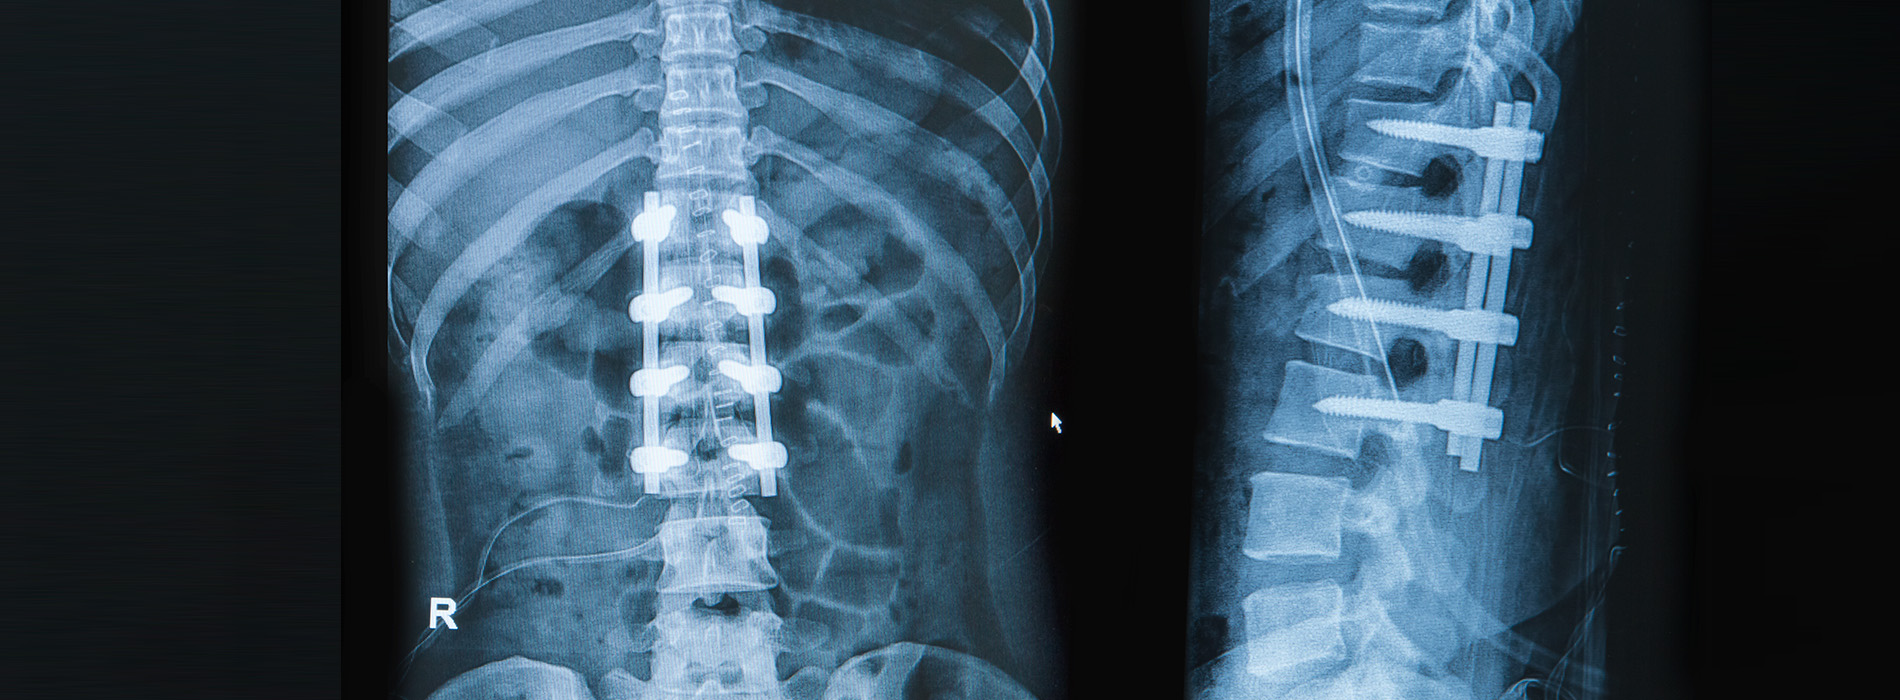

At its core, fusion replaces a painful, moving spinal segment with a stable construct that relies on bone healing. Surgeons commonly place a graft between vertebrae and secure the area with hardware—such as screws, rods, or plates—to maintain alignment during the healing process. Over time the graft incorporates and the vertebrae fuse into one solid mass, which stops abnormal motion that has been contributing to symptoms.

During the procedure, bone graft material is placed between the vertebrae to promote new bone growth. This graft can come from the patient (autograft), a donor source (allograft), or synthetics and biologic enhancers that support fusion. Metal implants such as screws and rods or plates are used to hold the spinal segment in the desired position while the graft heals. In many cases, instrumentation also restores or preserves spinal alignment.

Most fusion surgeries follow common stages: exposure of the spine, preparation of the bone surfaces, placement of graft material, and application of fixation devices to maintain alignment. Many surgeons now incorporate image guidance, minimally invasive retractors, and intraoperative monitoring to increase safety and accuracy. These tools allow precise implant placement and reduce risk to nearby nerves and tissues.

Hardware commonly includes screws, rods, plates and interbody cages that support alignment and compress the grafted area to encourage fusion, and implant selection is tailored to anatomy, bone quality and the surgical approach.